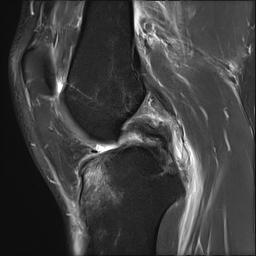

- MRI evidence of tibial / femoral peel off

- consider acute repair

Acute femoral peel off of PCL